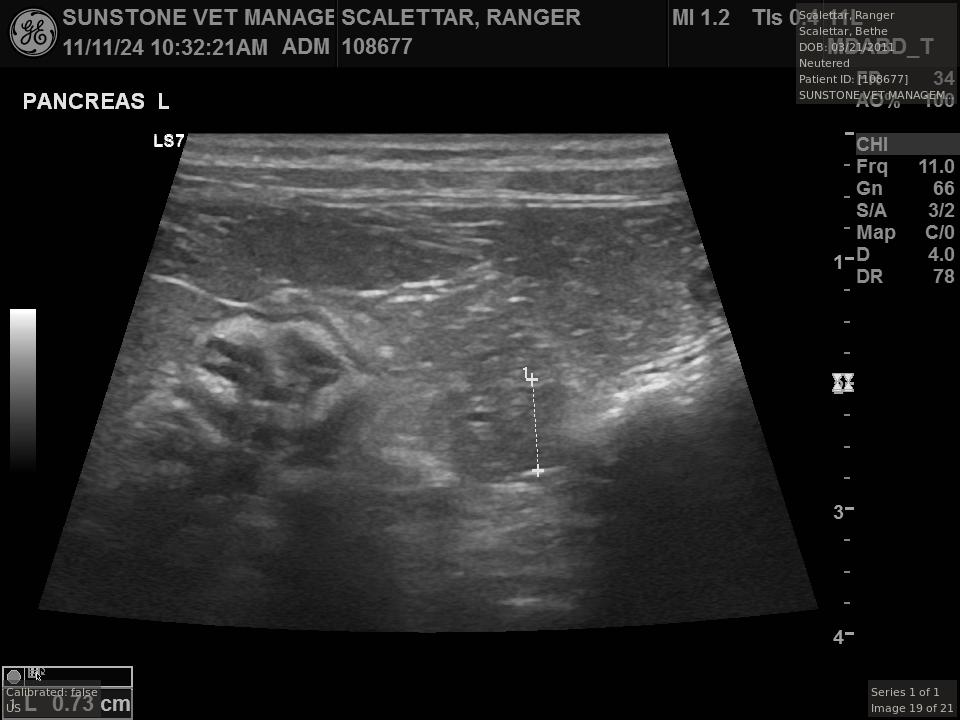

The veterinarian generated a series of images showing different organs and substructures by

changing the position and orientation of the ultrasound transducer. The images were collected

in a defined order, which is repeated from patient to patient, ensuring that nothing is missed. In

Ranger's case, the sonographer collected about twenty images during an examination that

lasted about fifteen minutes.

The sonographer stated that Ranger's ultrasound images were largely normal for an older cat. In particular, they show changes in the kidneys that are commonly noted in geriatric cats and that reflect a risk for the development of chronic kidney disease. However, the images did not show any significant abnormalities in Ranger's stomach, intestines, and associated lymph nodes. Nonetheless, the results did not rule out recurrence of Ranger's small cell lymphoma.